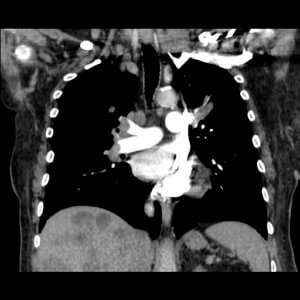

This image is from a pulmonary angiogram of the right lung, showing a PE at the beginning of the upper and lower lobe arteries.